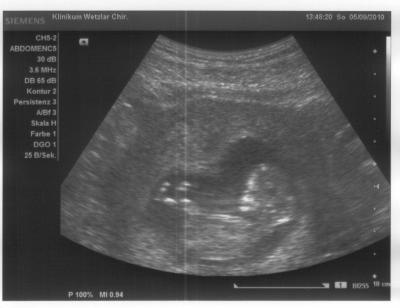

Wir habens auch vermessen, SSL heute 61,7 mm *staun*

Schönes Bildchen

Sehr schönes Foto :-) Im Moment habe ich ja auch noch das Glück, dass wir unseren Krümel einmal die Woche sehen können :-)

Hm, also das kann ich nicht so ganz glauben. Der menschliche Hörbereich umfasst Frequenzen bis max. 16 kHz. Ultraschall geht bis in den Gigahertzbereich, wir haben gestern mit 3,6 MHz geschallt, das ist weit oberhalb des hörbaren Bereiches, auch für Babys! Das was passieren KANN, aber nur bei hohen Energiedosen, ist eine Erwärmung des Fruchtwassers bei langer Beschallung. Bei den Frequenzen und Energiedosen, die ein Ultraschallgerät, wie es zum Schallen von Organen bzw. Babys verwendet wird, ist das aber quasi ausgeschlossen. Schädlicher ist aber übrigens ein Doppler der Plazentagefäße! Da sollte man schon abwägen, wie nötig das ist...